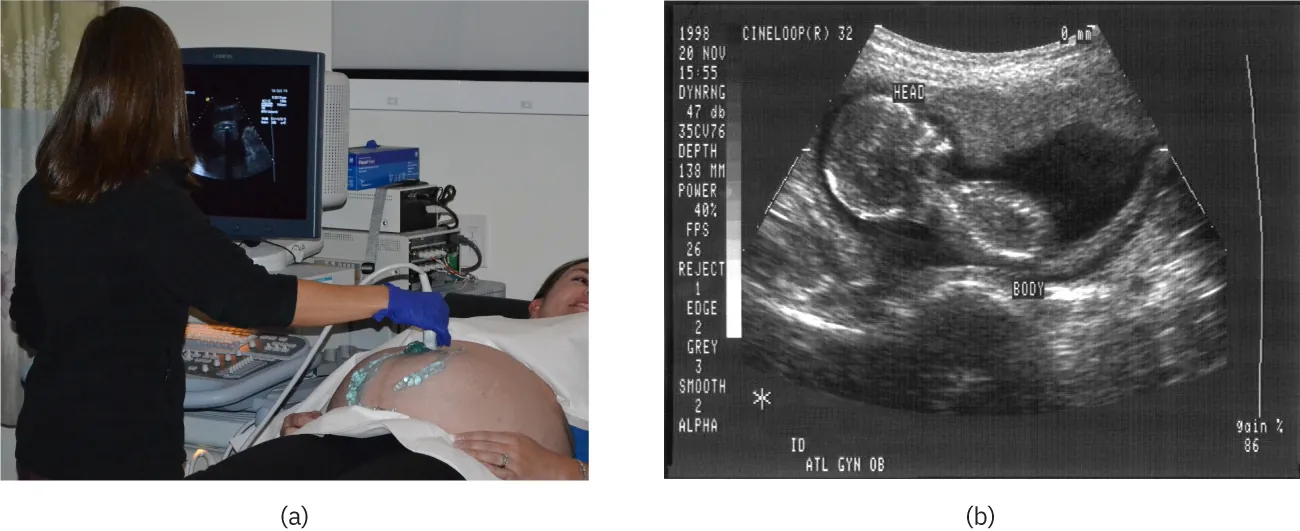

The most common ultrasound applications produce an image like that shown in Figure 17.43. The speaker-microphone broadcasts a directional beam, sweeping the beam across the area of interest. This is accomplished by having multiple ultrasound sources in the probe’s head, which are phased to interfere constructively in a given, adjustable direction. Echoes are measured as a function of position as well as depth. A computer constructs an image that reveals the shape and density of internal structures.

The first part of the diagram shows an ultrasound device scanning a woman’s abdomen. The second part of the diagram is an ultrasound scan report of the abdomen.

Figure 17.43 (a) An ultrasonic image is produced by sweeping the ultrasonic beam across the area of interest, in this case the person's abdomen. Data are recorded and analyzed in a computer, providing a two-dimensional image (credit: COD Newsroom, Flickr). (b) Ultrasound image of 12-week-old fetus. (credit: Public Health Image Library, CDC)